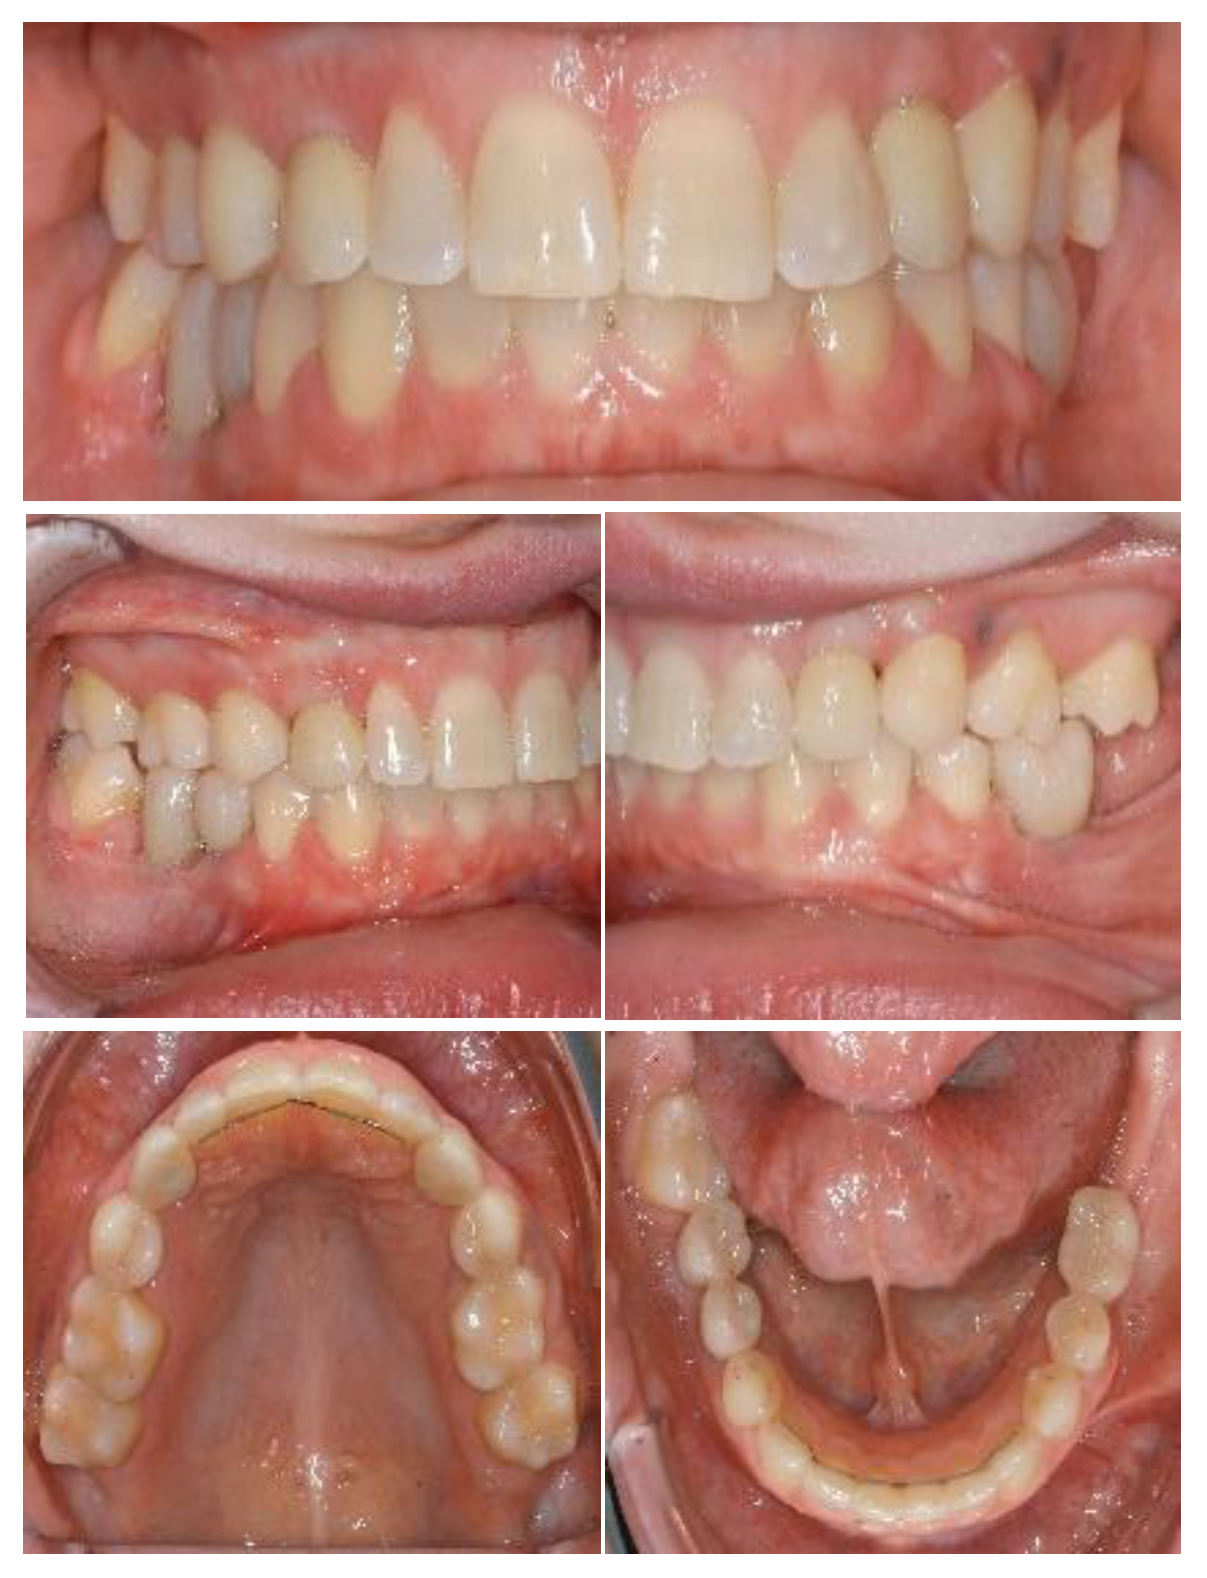

2.1. Case One

2.2. Case 2